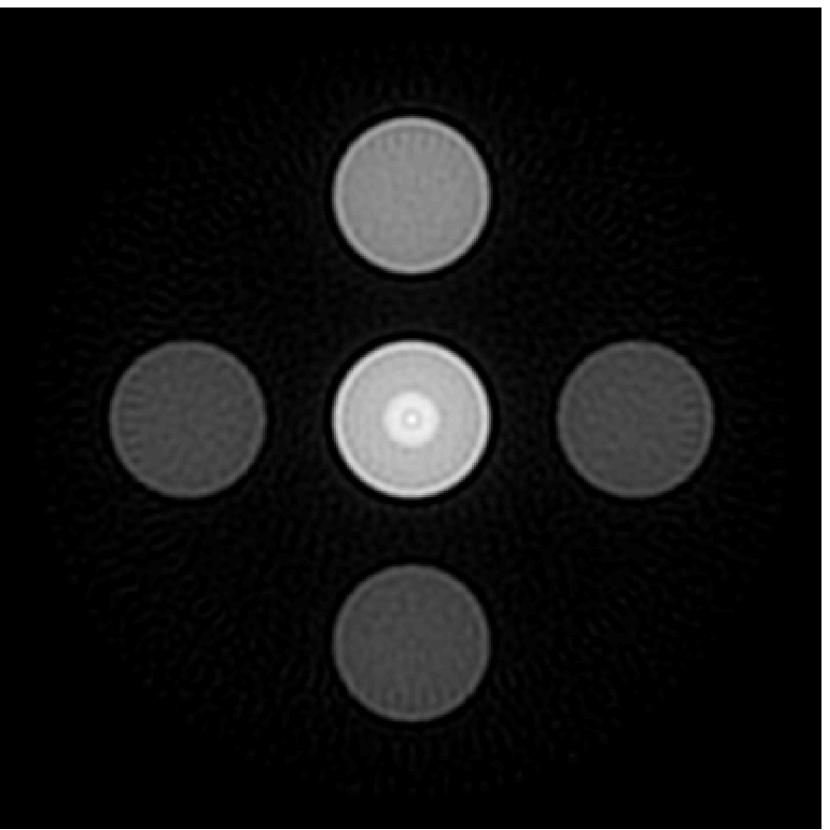

As shown in Figure 6, when the error in the EIR was small (e.g., as with the EIR in Figure 6(a)), images were reconstructed with high accuracy using the VP algorithm. When the perturbations in the EIR were stronger (e.g, as in Figure 6(c)), artifacts and distortions in the reconstructed images were still significantly reduced by use of the VP algorithm; however, larger values of the regularization parameters had to be applied. When as in the initial EIR in Figure 6(e), no improvement was observed in the image reconstructed by use of the VP algorithm.